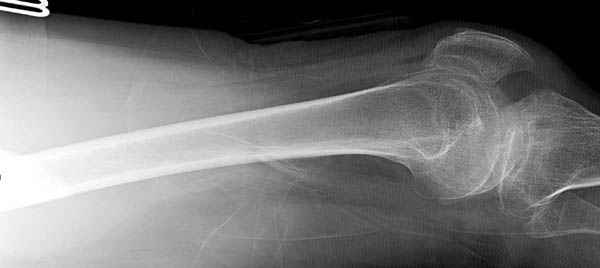

Среди русскоговорящих коллег Ортофорум стал одним из мест, где многие из нас черпают знания для решения своих ежедневных проблем в виде практических советов и обмена опытом. Кроме таких советов, Ортофорум стал источником новых познаний среди ортопедов, особенно по редко встречающимся состояниям в ортопедии. Продолжая традицию, я хотел бы представить редко встречающий случай перелома бедра у больного с гемофилией. Больному 42, гемофилия типа А, из истории упал с высоты около 1,5 метра, переправлен из другой больницы. По происхождению мексиканец, 10 лет назад по поводу артроза пр. коленного сустава в Мексике сделано протезирование, которое закончилось ампутацией выше коленного сустава. При поступлении бедро напряженное, сосудистых и неврологических расстройств нет. На рентгенограмме оскольчатый перелом бедра с вовлечением проксимальной спирали в шейку бедра. Хотели бы знать тактику ведения подобных больных и на что надо обратить внимание? Djoldas Kuldjanov, MD Department of Orthopedic Surgery St. Louis University Medical Center

Учитывая, что случай ургентный, больной поступил вечером, не стали делать вытяжение и срочно провели операцию по фиксации перелома бедра антеградным штифтом Versa Nail от DePuy.

Для профилактики дальнейшего раскола в шейке предварительно во время проксимального рассверливания спереди и сзади провели временные спицы, которые в дальнейшем были заменены на шурупы (miss nail method)